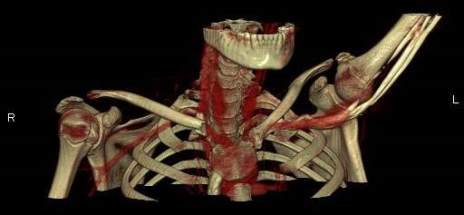

A Contrast CT with 3D CT reconstruction scan (Fig. 2, 3), confirmed the alignment of the floating fragment (rotated and with its medial end pointing posteriorly), which was causing compression on the right Brachiocephalic vein.

Fig. 2: Axial section from Contrast CT Scan showing compression of fracture on brachiocephalic vein

Fig. 3: Three-Dimensional Contrast CT Reconstruction

As our experience teaches, a correct and complete pre-operative evaluation (SC dislocations versus fractures; potential compromise of respiratory, neurovascular or other neighbouring structures) should be performed. Contrast CT imaging with three-dimensional reconstruction yields adequate information regarding neighbouring vasculature and alignment of the floating fragment [4, 5, 17], and is the modality of choice in an emergency setting. MRI, if available, and ultrasound imaging would in theory be ideal for the demonstration of articular and physeal anatomy and damage [5], and would have helped us in planning surgery better. Yet, direct surgical visualisation during open reduction provided similar information.